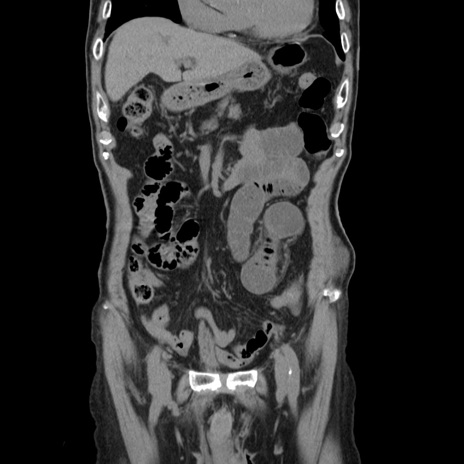

症例24(冠状断像)

【症例】80歳代男性

【主訴】左側腹部痛、嘔吐

【現病歴】本日早朝より左腹部に痛みあり。昼頃嘔吐認めたため、救急要請。

【既往歴】直腸癌(Mile手術)、胆摘

【身体所見】意識清明、BT 35.9℃、BP 221/93mmHg、SpO2 97%(RA) 、腹部:左ストーマ周囲に限局性の腹部膨隆あり。 膨隆部自発痛・圧痛あり・軟。

【データ】WBC 7700、CRP 0.09